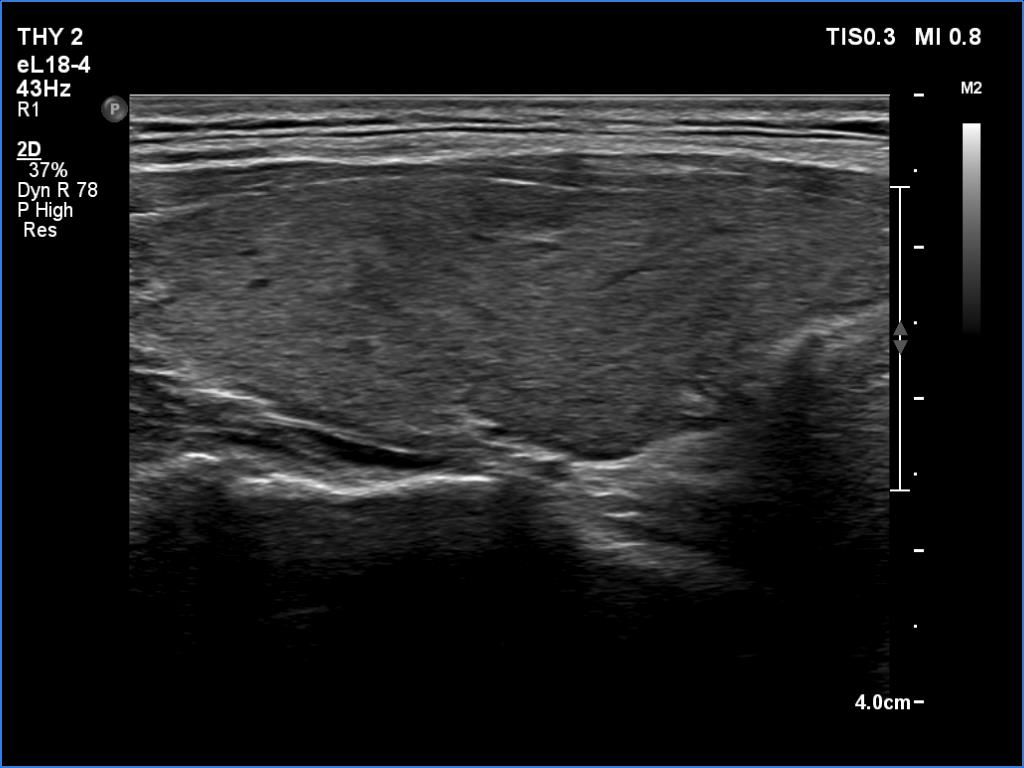

Left lobe, longitudinal scan

Clinical data: A 35-year-old woman was referred for a newly diagnosed hyperthyroidism. The patient had typical complaints, including elevated heart rate and weight loss.

Comment.

This is the typical course of a non-relapsing Graves' hyperthyroidism. As the hormone results improve, both the size of the initially enlarged goiter and the degree of hypoechogenicity decrease.